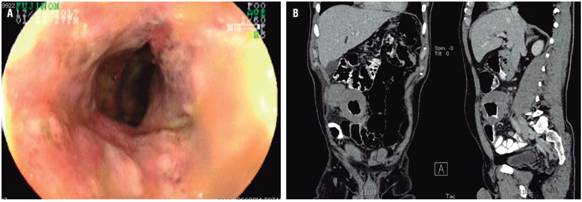

4 meses después refirió reaparición del dolor abdominal y distensión; en el examen físico se palpó una masa dolorosa a nivel de la fosa ilíaca derecha, por lo cual se repitió una colonoscopia total en la que se encontró mayor engrosamiento en el íleon distal y úlcera circunferencial (Figura 3 A), y en la tomografía axial computarizada (TAC) de abdomen contrastado se reportó lesión pseudotumoral en el íleon distal hasta la válvula ileocecal (Figura 3 B); se programó para resección en cirugía. Se describió una lesión de aspecto tumoral, por lo que se realizó ilectomía y hemicolectomía derecha resecando casi 40 cm (Figura 4), con anastomosis ileotransversa. En patología se encontró neoplasia de estirpe hematolinfoide (linfoma B difuso de células grandes), lesión de 8 cm, compromiso desde mucosa hasta serosa, bordes de resección libres de tumor, sin invasión vascular ni perineural; y ganglios negativos (Figura 5 A, B y C).